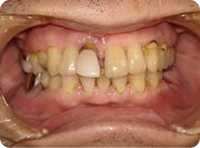

施術例②

治療前

前歯が歯周病のためグラグラで今にも抜けてしまいそうな状態です。

治療後

抜歯と同時にインプラントを植立し、3ヵ月後にセラミックの冠を装着しました。

治療前と治療8ヵ月後のレントゲン写真です。

手術時に足した人工骨も安定しています。